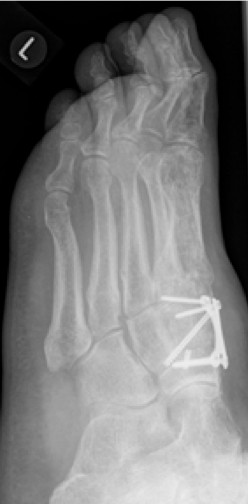

Die indizierte Operation wurde im Februar 2017 durchgeführt. Die Stabilisierung der Arthrodese erfolgte mit insgesamt 3 Schrauben und Anlagerung vom Knochenersatzmaterial.

2.-Postoperatives Bild Februar 2017